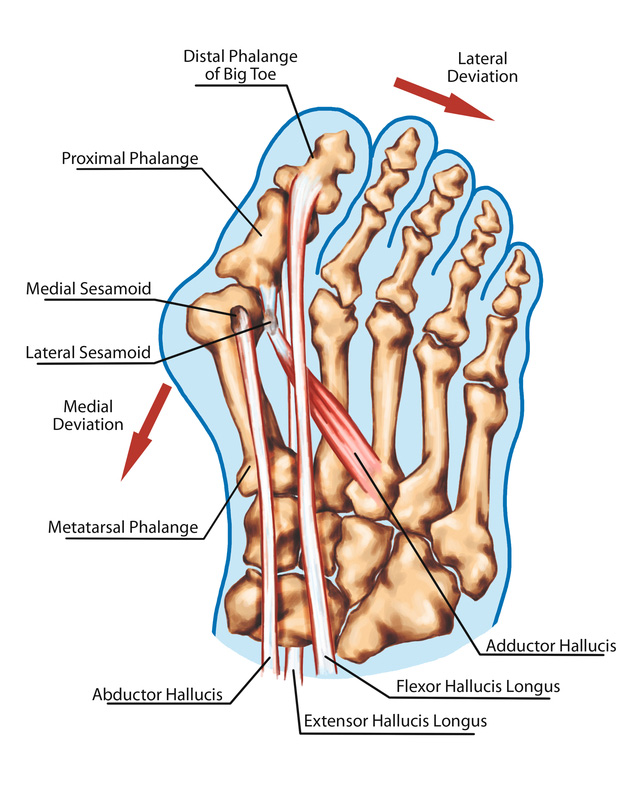

Плюснефаланговом суставе ноги

Плюснефаланговом суставе ноги 114 фото